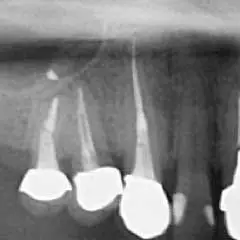

なぜなら、根管は非常に複雑に入り組んでおり、しっかり清掃を行わなければ、「痛み」「腫れ」などの原因となり、「根尖病巣」という病気にもなるためです。

下の画像ですが、「黒い部分」が神経の入っている管であり、このすべてを綺麗に清掃する必要があります。

従来までは、「肉眼」でこの治療を行っていました。

しかし、上記画像のように、神経が入っている管は非常に複雑に入り込んでおりますので、「肉眼」ではしっかり作業することは不可能です。つまり、従来法の根管治療とは「勘」や「経験」に頼った治療で、時には「再治療」そして「抜歯」の選択を迫られることも多々ありました。